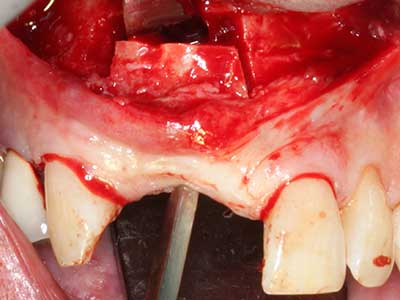

Fig. 14: Placement of four tapered RSX implants (Bego Implant Systems, Bremen).

Indication: Bone splitting

Bone tissue is not simply a mineral structure but also contains a substantial proportion of collagen fibres. This means it not only has good compressive strength but also a degree of flexibility, which can be taken advantage of when performing bone augmentations. In the classical expansion procedure using bone splitting, the atrophied alveolar ridge is split longitudinally and carefully expanded after reaching an adequate osteotomy depth (Fig. 13-16), ideally without substantial removal of the periosteum (Brugnami, Caiazzo et al. 2014, Stricker, Fleiner et al. 2014). Screw and plate systems with increasing expansion distance have proven effective in separating the two bone lamellae while remaining below the fracture threshold. In general, residual bone widths of at least 3–4 mm are required (Chiapasco, Zaniboni et al. 2006) to guarantee adequate flexibility and sufficient bone coverage of the future implants. If necessary, a vertical relief osteotomy on one or both sides can improve flexibility. A combination with additional augmentation techniques, particularly on the buccal side, has been described as an alternative to the classical technique.

The splitting procedure is particularly atraumatic and there is no significant loss of dimension when using piezosaws, and there are no significant differences between implants in split jaws and implants in an alveolar ridge without a bone deficit (Chiapasco, Zaniboni et al. 2006, Danza, Guidi et al. 2009). However, sufficient continuous irrigation is essential, particularly with locally restricted and deep splitting to prevent thermal stress in the apical osteotomy regions.